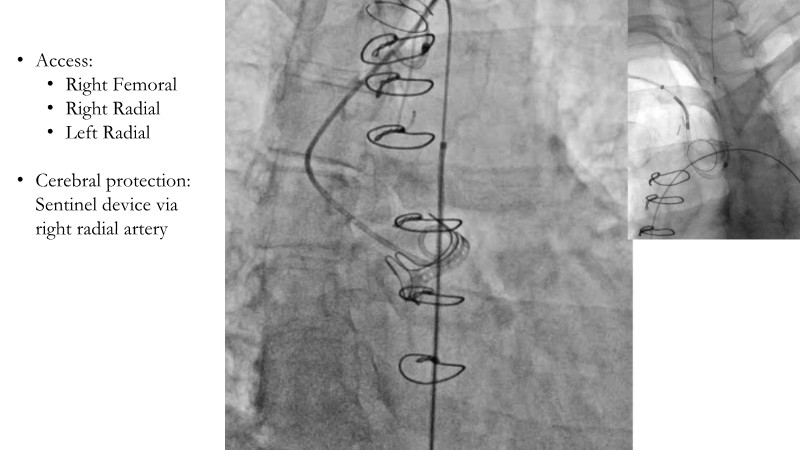

This session explores the evolving landscape of transcatheter aortic valve implantation (TAVI) with a focus on supra-annular valve technology. It covers techniques for achieving commissural alignment, considerations for small aortic annuli, and advantages in treating bicuspid aortic valve disease, supported by clinical data and illustrative cases.

- To learn how to perform TAVI resulting in commissural alignment and easier coronary access